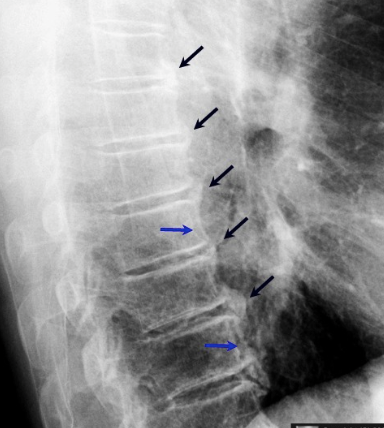

what are the radiographic findings of DISH

cf ankl spon

marginal syndesmophytes, bamboo spine, ossificiation of disc space, osteopenia, strong assoc wiht HLA b27, younger pts, bilateral sacroilitis